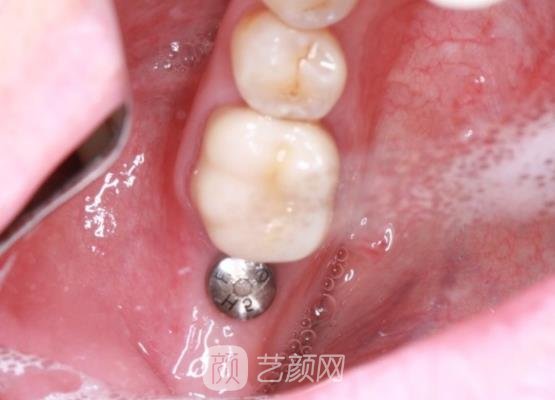

方案制定好之后,医生就开始了手术,手术过程中因为采用了麻药的处理,所以我也没有感觉到什么剧烈的疼痛感,只是可以隐约的感觉到我的牙龈处肌肉一直在蠕动,手术也是比较方便的,几个小时以后就结束了。

手术刚结束,我的牙龈出了一点血,还有一些疼,医生告诉这些情况比较正常,几天以后就会好了,让我不用太过于担心,然后又给我开了一些消炎药,让我定时服用,果然吃点消炎药以后,我的疼痛感觉也就基本上消失了。

几个月以后我的种植牙已经恢复的自然了,现在可以看到我的种植牙就像是我自己的牙齿一样,基本上找不到人工手术的痕迹,而且我的口腔也没有一些异物的感觉,后期也没有出现什么特殊情况,手术成果真的让我很满意。